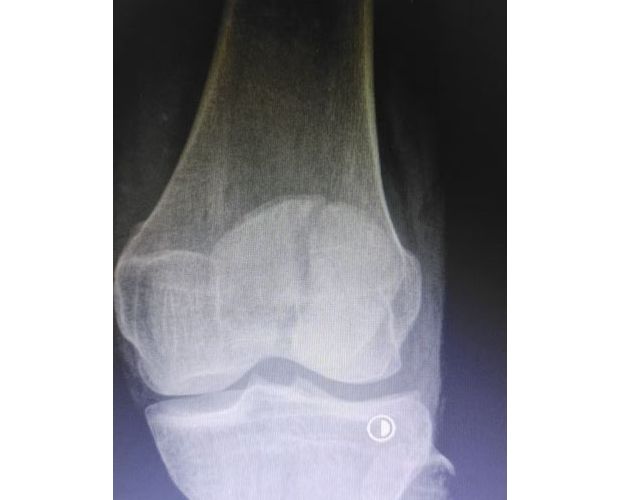

該患者因意外外傷導(dǎo)致髕骨骨折后,緊急前往何店鎮(zhèn)中心衛(wèi)生院就診。該院外科醫(yī)護(hù)團(tuán)隊(duì)迅速響應(yīng)、規(guī)范處置,第一時間為患者完善各項(xiàng)術(shù)前檢查,全面細(xì)致評估患者身體狀況及骨折傷情,精準(zhǔn)把握手術(shù)指征。為最大限度保障手術(shù)安全與治療效果,切實(shí)減少患者往返城區(qū)醫(yī)院的奔波之苦,降低就醫(yī)成本,該院立即啟動醫(yī)共體專家協(xié)作機(jī)制,正式向曾都區(qū)人民醫(yī)院申請專家技術(shù)支持。接到申請后,徐三軍主任快速響應(yīng)、主動下沉,帶著豐富的臨床經(jīng)驗(yàn)和精湛的手術(shù)技術(shù)趕赴衛(wèi)生院,與該院外科醫(yī)護(hù)團(tuán)隊(duì)深入研討,結(jié)合患者具體病情制定個性化手術(shù)方案,細(xì)致梳理術(shù)前各項(xiàng)準(zhǔn)備工作,為手術(shù)順利開展筑牢堅(jiān)實(shí)基礎(chǔ)。